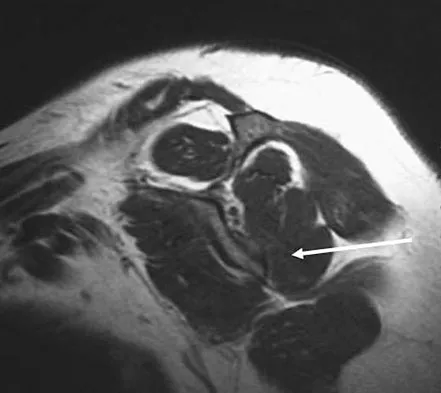

Figures 10a through 10c show the plain radiograph and MRI scans of a 41-year-old man who has right hip pain. What is the most likely diagnosis?

Explanation